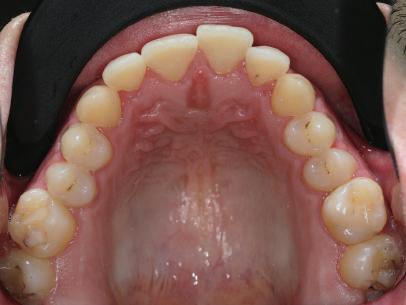

Пациентът постъпи в клиниката с молба за тотална рехабилитация на усмивката. Той не харесваше централ ните си резци, които според него бяха твърде къси и квадратни. Имаше раз стояние от медиално и дистално на латералните му резци. Друго сериоз но оплакване бе свързано с металоке рамичната корона на зъб 12, която бе жълтеникава и неестетична, като цяло не харесваше вида на венците си и както самият той се изразяваше, „вижда се прекалено много от венците при усмивка“.

След диагностиката бяха направени екстра- и интраорални снимки, както и рентгенографии; професионалното почистване бе от изключителна важ ност, бяха дадени и инструкции за лич на орална хигиена. Бе направено интра орално сканиране с Medit i500. Цялата тази информация бе използ вана в приложението Smilecloud за 2D биометричен дизайн. В приложението са налични естест вени форми на зъбите и щом бяха под брани зъби и бе направен дизайн

библиотеката на Exocad. Струва си да се отбележи, че 2D дизайнът от Smile Cloud бе спазен до последния детайл в Exocad smile creator с цел да се създаде 3D obj файл със зъбните форми. След като естетичният дизайн бе готов в model creator модула на Exocad, адитивен 3D мок-ъп модел бе експорти ран и принтиран от принтер Formlabs 3. Моделът бе използван за направата на силиконов водач, за да се изготви мо тивационен мок-ъп в устата на паци ента и да се оценят естетичните па раметри. След като пациентът одобри вида на усмивката си, мок-ъпът бе използван за финализиране дизайна на усмивка та. Мок-ъпът бе използван също така като водач по време на мекотъканна та хирургия, както и при препарация на зъбите.

Препарираните зъби бяха импорти рани в Exocad и насложени върху ес тествените форми от биометричния дизайн, като така стана ясно дали зъ бите са били препарирани коректно. По този начин зъболекарят и зъботехни кът работят в една и съща екосистема и резултатът е оптимален. С короната се справихме чрез диги тална редукция на циркония в Exocad, като по този начин на практика създа дохме циркониево кепе, след което про изведохме фасета от IPS Empress Cad Multi. Кепето от Katana Zirconia на зъб 12 с букално послойно нанесена керами ка бе фрезовано (послойното нанасяне бе направено, за да се подобри връзката и да се осигури адхезивно циментиране на фасетата към циркониевото кепе, както и за да се напасне цветът към този на съседните зъби). При първото сканиране регистрирах ме цялата горна зъбна дъга, така че, ко гато се наложи да сканираме повторно, бе изтрит и сканиран наново само зъб 12, тъй като венците не бяха отдръп нати при второто сканиране.

рентгенографии. Инициална терапия и професионално почистване. Интраорално сканиране с цел диги тално планиране. Регистрация и 3D ориентиране на ок лузалната равнина на горна и долна челюст в пространството. 2D дигитално планиране и дизайн на усмивката посредством приложение то Smile Cloud. 3D дигитално планиране и дизайн на функционалните и естетичните па раметри. 3D дигитален дизайн и адитивен мокъп на горна челюст. 3D принтиране и мок-ъп модели. Мотивационен мок-ъп. Фини корекции за постигане на фи налния дизайн. Мекотъканна хирургия с мок-ъпа като водач Препарация през мок-ъпа, използвай ки дизайна като водач за финалната препарация в Exocad. Циркониево кепе ще бъде циментира но с цел адхезивно залепяне на фасе та на края. Кепето има същия цвят като този на съседните зъби, за да може фасетата да се впише перфект но в цялостната усмивка. Изработване на 12 IPS Empress Cad Multi фасети с послойно нанесена ке ТОТАЛНА РЕХАБИЛИТАЦИЯ НА УСМИВКАТА С ИЗЦЯЛО ДИГИТАЛЕН ПРОТОКОЛ Д-р Калин Маринов и зт. Стефан Петров рамика букално върху зъбните препа рации и върху първичното циркони ево кепе (има възможност за ецване и адхезивно

Една седмица след препарацията на зъбите и циментирането на цирко ниевото кепе бяха изработени 12 IPS Empress Cad Multi фасети. Макро- и микротекстурата на фасе тите бяха направени на ръка, след кое то бяха нанесени 3D характеризации с боички, а полирането отново бе напра вено ръчно, за да им се придаде естест вен и естетичен вид. Предизвикателството тук беше короната да има същите оптични характеристики като тези на остана лите зъби при естествена светлина, през поляризационен и флуоресцентен филтър. 3D принтерът бе Fromlabs, софтуерът за фрезоване – Mill Box, а фрез апаратът –imes icore CORiTEC 350i. В крайна сметка постигнахме ес тествен вид на усмивката с натурал на зъбна морфология при изцяло диги тален протокол, при който дизайнът бе направен първоначално и през всич ки етапи на лечението се придържахме към него до самия край Излишно е да отбелязваме, че всички сме удовлетворени от постигнатото! Преди След Победител в категория „Клиничен случай с изцяло дигитален протокол“ в конкурса „Усмивка на годината 2022“